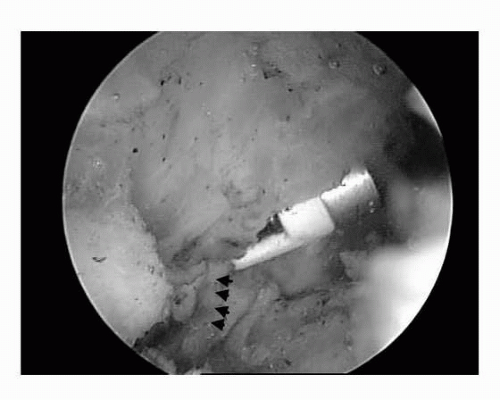

For ac joint pain, a small bur is used for removal of bone spurs and diseased bone in the joint to prevent the ends of the bone from grinding together. Common symptoms of ac joint osteoarthritis are pain in the top of the shoulder that radiates toward the neck and shoulder stiffness. Surgery involves the use of arthroscopic instruments to trim or remove the bone spur and open the joint space.